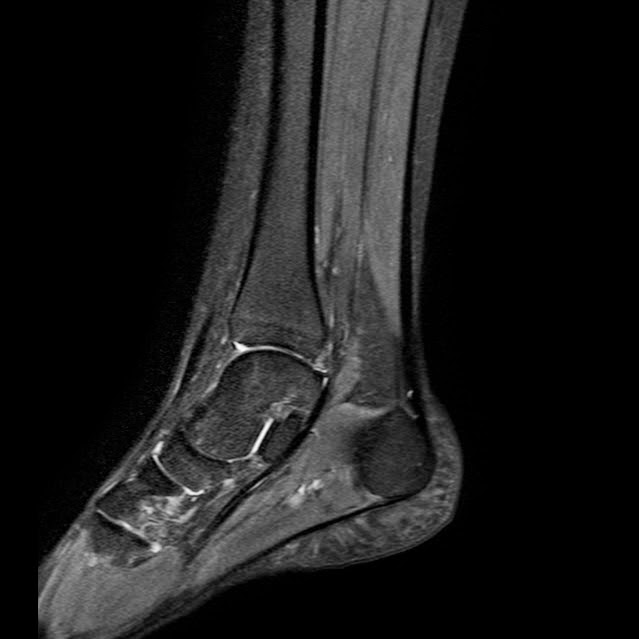

Caso interesante #3

Paciente 1 (Caso de referencia)

Masculino 17 años

Caso interesante # 3